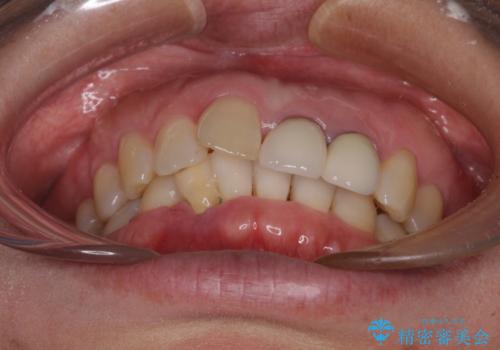

- 下顎前歯が抜けそうとのことで来院された患者様です。

初診の状態ではすぐにでも抜けそうな状態で、インプラントによる補綴治療を行うこととしました。

インプラント治療に際し、前歯の叢生に対する矯正治療を提案したところ、興味を持たれたので、インビザライン・ライトによる矯正治療を行うこととしました。

抜歯後にスペースができると恥ずかしいため、抜歯した歯を接着剤で固定した上で矯正治療を行い、その後インプラントやオールセラミッククラウンの装着を行うこととしました。